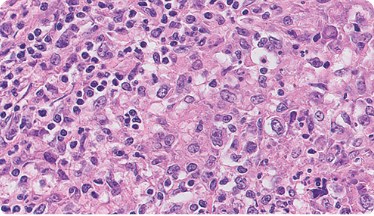

CCEE = carcinoma de células escamosas de esófago; H&E = hematoxilina y eosina.